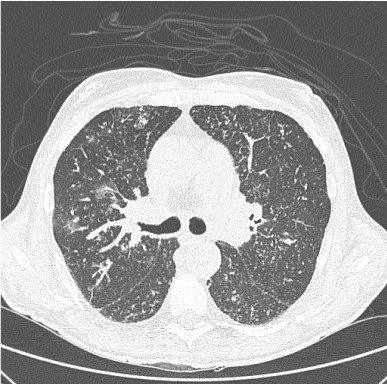

An 81-years-old patient presented himself with dyspnea on exercise and dry cough, for 3 months. He was being treated to Waldenström's Macroglobulinemia in the prior 6 months and had non-requiring dialysis chronic renal failure as a consequence of the disease. High-resolution CT scan showed pulmonary micro-nodules with some predominance in the bronchial-vascular axis (Figure 1). Due to the findings in the CT scan and the high prevalence of the disease in Brazil, the patient was being treated empirically as having miliary tuberculosis and presented several side effects following the therapy, such as liver toxicity and Steven-Johnson's dermatitis. He was then referred to our service and submitted to transbronchial biopsy that showed the presence of pulmonary ossification in the nodular form (Figure 2), quite possibly secondary to renal failure or to amyloidosis. Tuberculosis drugs were removed, and the patient improved the respiratory symptoms with further therapy to Waldenström's Macroglobulinemia and diuretics [1,2].

Figure 1: CT scan demonstrating pulmonary micro-nodules with some predominance in the bronchial-vascular axis and scarce ground glass opacities.